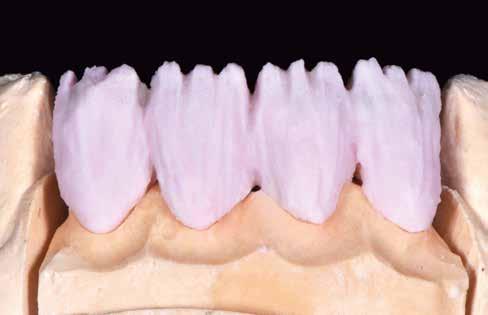

ás, majd #0-ás retrakciós fonalakat (Ultrapak, Ultradent Products Inc, South Jordan, Utah, Egyesült Államok) helyeztünk. A végső precíziós lenyomatot polivinil-sziloxán lenyomatanyaggal (Virtual 380, Ivoclar Vivadent AG, Schaan, Liechtenstein) vettük. A fogtechnikai fázisban ultravékony (0,5 mm-nél vékonyabb) földpátkerámia héjak elkészítését kértük (Super Porcelain Ex-3, Kuraray Noritake Dental, Tokió, Japán), (7. ábra). A kerámia héjak készre vitelét követően a próba során a héjakat a helyükre illesztettük a széli zárást, az így kialakított fogformák ellenőrzése céljából. A páciens elégedett volt az így kapott látvánnyal. A végleges ragasztás kofferdám izolálásban történt. A preparált fogak felületét először 37%-os foszforsavval (Total Etch, Ivoclar Vivadent) 15 másodpercen keresztül kondicionáltuk, majd vízzel leöblítettük (8. ábra). A kondicionált zománcfelszíneket Adhese Universal (Ivoclar Vivadent) adhezívvel kezeltük. A kerámiahéjak homorú felszíneit 5%-os folysavval (IPS Ceramic Etching Gel, Ivoclar Vivadent) 20 másodpercen át kondicionáltuk, majd a felszíneket Monobond Plus primerrel (Ivoclar Vivadent) vontuk be (7. és 8. ábrák). A héjakat fényre kötő rezinalapú ragasztócement (Variolink Esthetic LC, Ivoclar Vivadent) applikálását követően a helyükre illesztettük. A kifolyó cementfelesleg eltávolítását követően minden felszínt (labiális, palatinális, meziális és distális) LED-es polimerizációs lámpával (VALO Cordless, Ultradent) 40 másodpercen keresztül megvilágítottuk.

Az elmúlt években a fogtechnikai eljárások fejlődésének köszönhetően lehetőségünk van nagy szilárdságú kerámiákból készülő ultravékony kerámia héjak készítésére.20 Jelen esetben, a kimagasló esztétikai tulajdonságainak köszönhetően, a földpátkerámiára esett a választásunk. Azt is fontos azonban kiemelni, hogy jelenleg csak kisszámú esetismertetésben találkozhattunk földpátkerámiából készült ultravékony héjakkal. Egy anyagtani vizsgálatban arról számoltak be, hogy az ultravékony (0,5 mm-nél vékonyabb) kerámiahéjak töréssel szembeni ellenálló képessége lehetővé teszi a klinikai felhasználásukat.21 Az utóbbi időben a rezin alapú ragasztócementek kötő- és mechanikai ereje javult18,22, ezáltal az ezekkel az anyagokkal rögzítésre kerülő restaurátumok